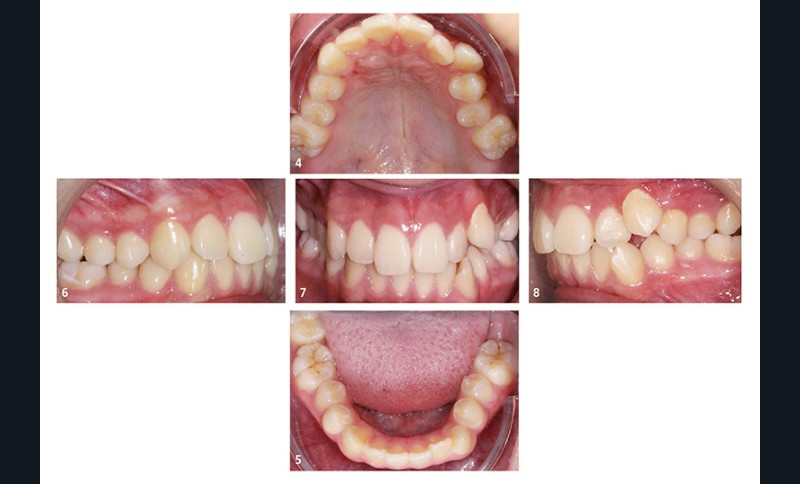

Sur le plan dentaire, au maxillaire, le patient présente une arcade en lyre avec de nombreuses malpositions (fig. 4). À la mandibule, la 37 est absente de l’arcade (fig. 5). Le patient présente une classe I d’Angle droite et gauche (fig. 6 et 7). Le surplomb et le recouvrement sont satisfaisants, les milieux sont alignés, et il existe une occlusion inversée 22/33 (fig. 8).